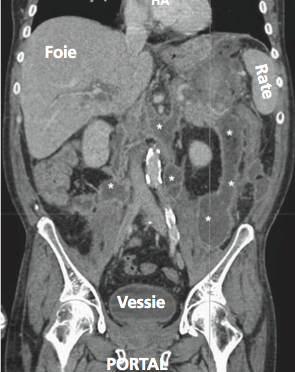

Figure n°6 : Pancréatite aigue balthazar E

(* = coulées de nécrose)

En pratique clinique, une TDM abdominale est le plus souvent réalisée à la phase initiale afin de poser le diagnostic de pancréatite. Il faut donc dans les formes graves, réaliser une seconde TDM à la soixante-douzième heure permettant alors d’évaluer l’étendue des coulées de nécrose. En cas d'une pancréatite aiguë "rassurante" sans aucun signe de gravité, il faut réaliser l'échographie lors de la prise en charge mais la TDM abdominale doit être réalisée seulement à la soixante-douzième heure

Ce score de Balthazar doit être abandonnée au profit de sa seconde version chiffrée selon l'indice de nécrose. Un stade supérieur ou égal à 4 est associé à un risque plus important de complications, notamment la survenue d’abcès pancréatique et de décès